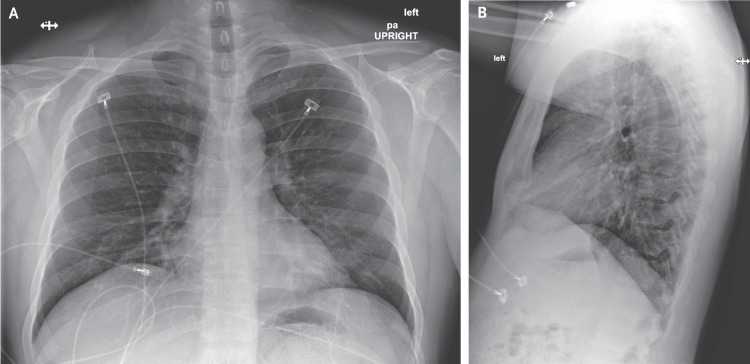

Description:An outbreak of novel coronavirus (2019-nCoV) that began in Wuhan, China, has spread rapidly, with cases now confirmed in multiple countries. We report the first case of 2019-nCoV infection confirmed in the United States and describe the identification, diagnosis, clinical course, and management of the case, including the patient's initial mild symptoms at presentation with progression to pneumonia on day 9 of illness. This case highlights the importance of close coordination between clinicians and public health authorities at the local, state, and federal levels, as well as the need for rapid dissemination of clinical information related to the care of patients with this emerging infection.